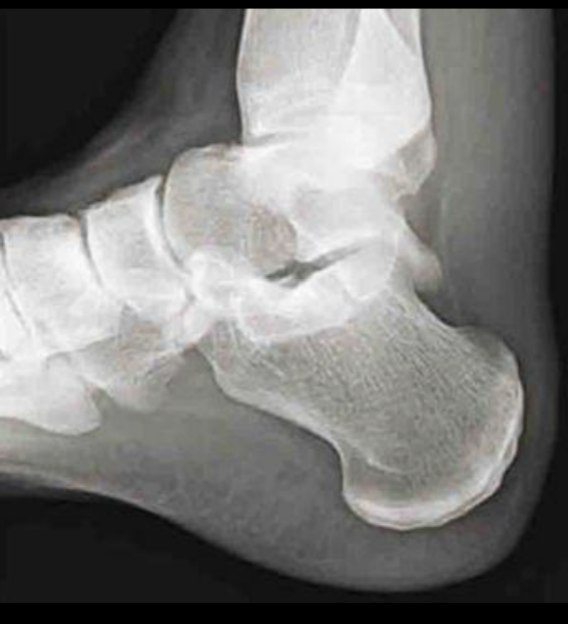

A

Normal Triangulo de Kager